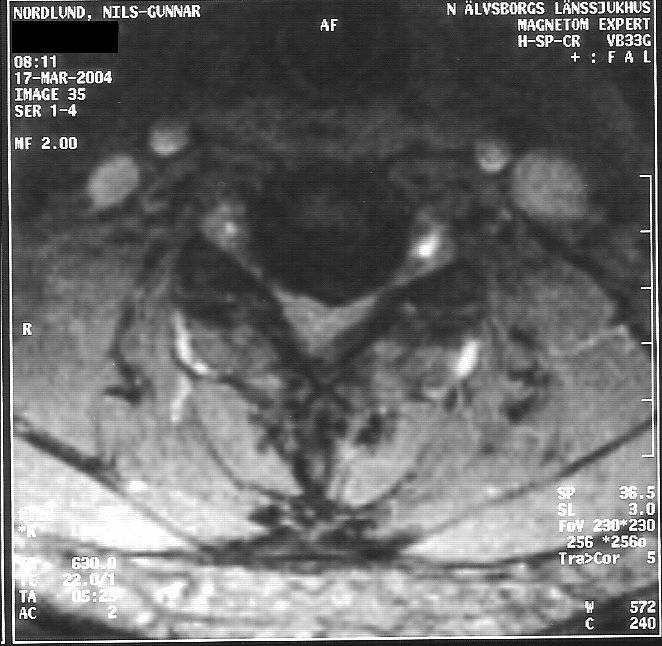

Jag bifogar även ett antal, av mig digitaliserade bilder från MR, 2004-03-17;

Bild 35